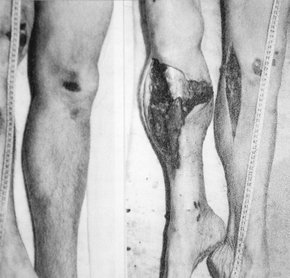

Az elsődleges ütközési nyomok az elütés során általában a lábszárakon keletkeznek, ami logikus, hiszen az autó orrának legkiállóbb része éri el először a sértettet. Ez lehet ugyan a lámpa, a sárvédő, vagy a gallytörőrács – vagy a jelvény, hiszen bármely, magára valamit is adó belvárosi boncmester látott már Mercedes-emblémát vérbeszűrődés formájában a bőrre rajzolódni –, de leggyakrabban mégis a lökhárító bombázza le a végtagot. A legenyhébb esetekben csak zúzódások, bőr alatti bevérzések, olykor kiterjedt hematómák tarkítják a traumatológián látott képet, erősebb ütközésekkor egy-egy csont el is törik, de a sérülés általában bőrrel és lágyrészekkel fedett. Könnyen kezelhető, csak ritka, kivételes esetekben tragikus balesetek ezek.

Kicsit erőteljesebb ütközés (30-35 km/h) során jön fel a találati listára az örök klasszikus, a nyílt törés, aminek az egyik legszembeötlőbb tulajdonsága, hogy a sértett, a szemtanú és a mentőorvos közül egyik sem szereti. Az okok prózaiak: eszméletvesztéshez vezető fájdalommal jár, látványnak a nyúzott izomcafatok közül kikandikáló törött csontvégek sem a legbarátibbak, végül igen veszélyesek is: az éles végű csontdarabok nem ritkán kaszálnak el nagy vérhozamú ütőereket, amikből – megfelelő kezelés nélkül – pár perc alatt el tud vérezni az illető. Az emberek fejében ritkán realizálódik, de egy gyalogos baleset során egyetlen nyamvadt nyílt lábszártörésből is meg lehet halni.

Innen csupán pár milliméternyi gázpedálmozgással el lehet érni a repesztett sérülésekig. Egy bizonyos sebességküszöb felett ugyanis olyan pokoli energiamennyiség érkezik a lábra, hogy a hirtelen szöveti nyomásnövekedés miatt a vádli egyszerűen felrobban. A látlelet nagyon hasonló a régi háborús, taposóaknás sérülésekre, igaz, a hőhatás elmaradása miatt itt egy sóhajnyival több a vér. A csonttörés ilyenkor is alap, a folyamat energetikáját tekintve a sértett általában nem ér be élve a kórházba.

Önmagában szintén jellegtelen, de a gázolásos balesetekre nagyon jellemző sérülés a nyúzásos, vagy úgynevezett décollement elváltozás. A testen áthaladó kerék a bőrt ilyenkor maga alá gyűri, túlnyújtja, a bőr alatti lágyrészeket leválasztja a bőr aljáról. A kialakult tasak hamar megtelik vérrel és roncsolt zsírszövettel – utóbbiból balszerencsés esetben zsírembóliát kaphat a sértett. A dolog veszélye az, hogy a tasak mérete nehezen megállapítható, így az elvesztett vér mennyiségére is nehezen lehet asszociálni, az adekvát kezelés késhet.